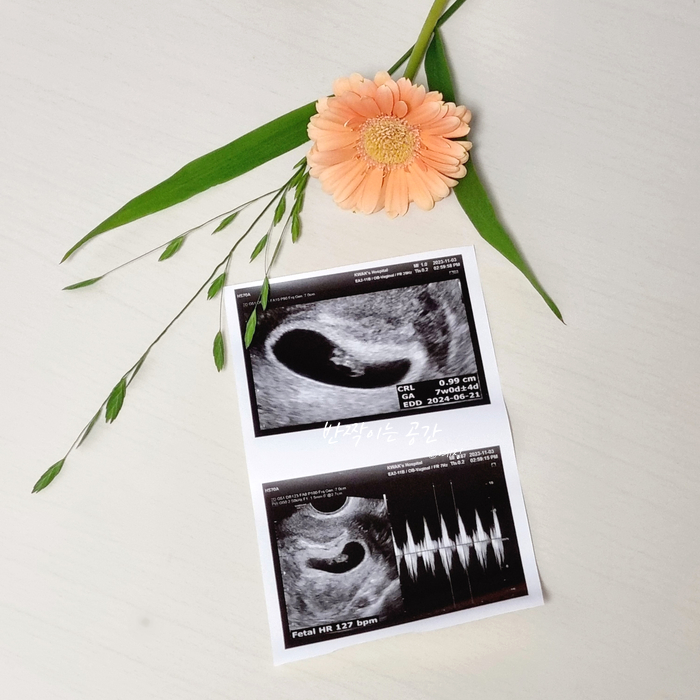

임신 6~7주차 :: 초음파 / 소화불량 / 입덧증상

6주차 룰루 이제 임산부뱃뱃지를 달고 다니는 나는야 임산부~ 하지만 저 임산부뱃뱃지... 아무 쓸모 없다.....